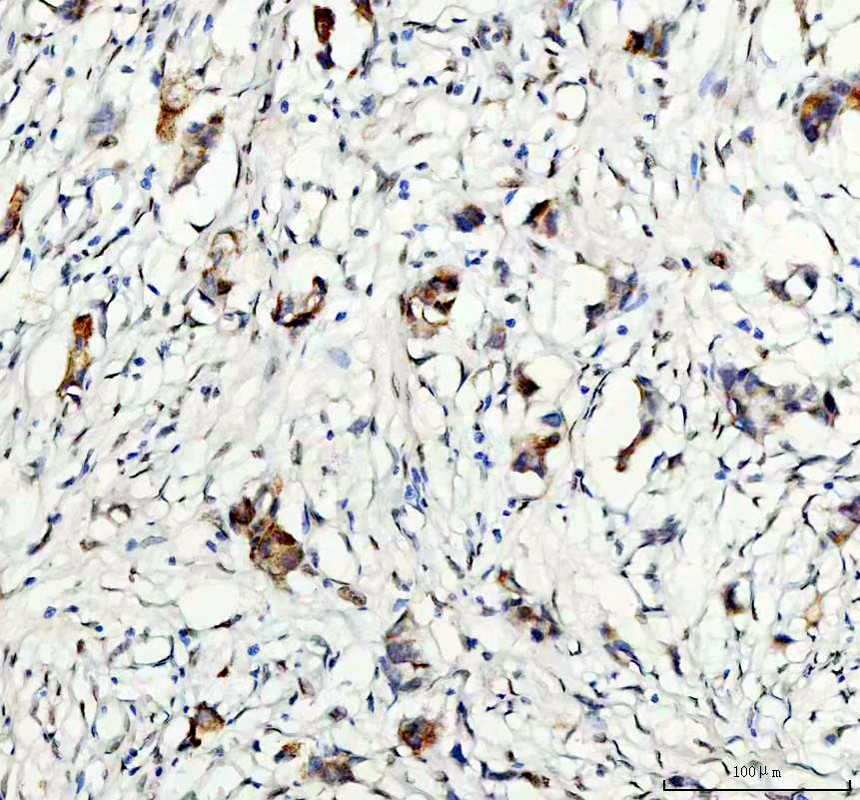

IHC analysis of GSK3B using anti-GSK3B antibody (A00791-3) .

GSK3B was detected in a paraffin-embedded section of human breast cancer tissue. The tissue section was incubated with rabbit anti-GSK3B Antibody (A00791-3) at a dilution of 1:200 and developed using HRP Conjugated Rabbit IgG Super Vision Assay Kit (Catalog # SV0002) with DAB (Catalog # AR1027) as the chromogen.

IHC analysis of GSK3B using anti-GSK3B antibody (A00791-3) .

GSK3B was detected in a paraffin-embedded section of human breast cancer tissue. The tissue section was incubated with rabbit anti-GSK3B Antibody (A00791-3) at a dilution of 1:200 and developed using HRP Conjugated Rabbit IgG Super Vision Assay Kit (Catalog # SV0002) with DAB (Catalog # AR1027) as the chromogen.